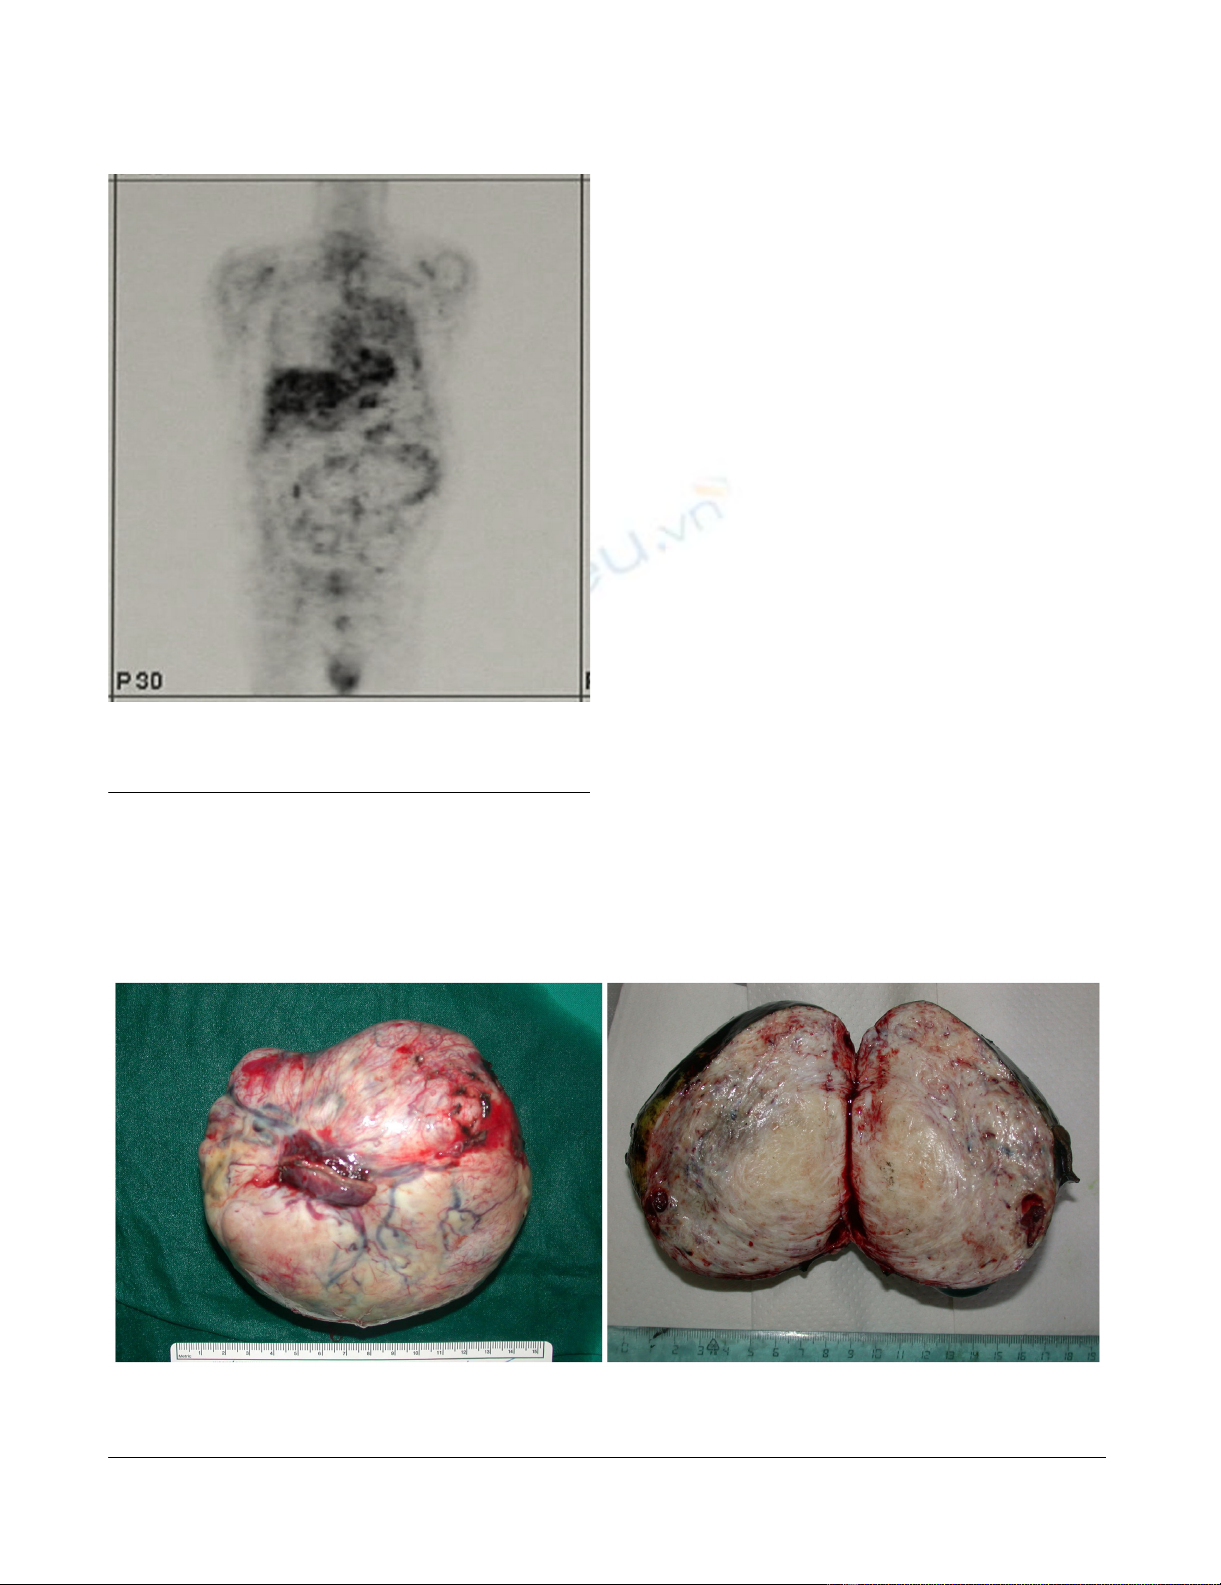

Moderate activity of the mass on Positron Emission Tomog-raphy studyFigure 2

Moderate activity of the mass on Positron Emission Tomog-

raphy study.

Left panel: surgical specimen with detail of the wedge resection of the lingulaFigure 3

Left panel: surgical specimen with detail of the wedge resection of the lingula. Right panel: solitary fibrous tumor of the pleura,

whorled fibrous tissue is evident on the cut section.